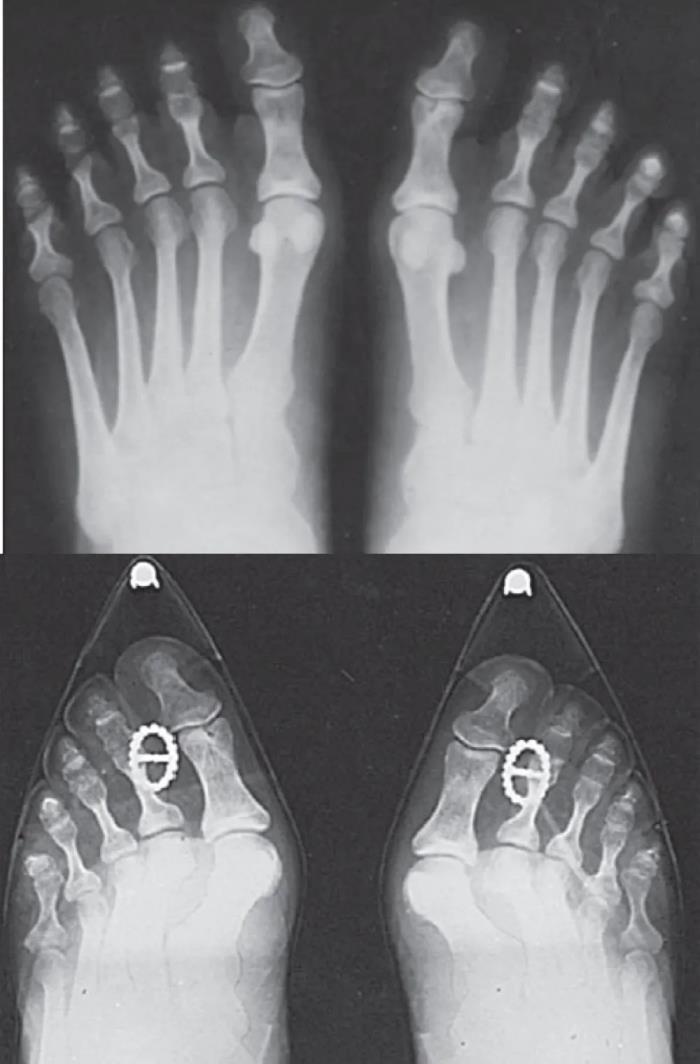

拇外翻是最常见的足踝部畸形疾病,在某些地方上也叫大脚骨病。主要表现为大脚趾向外偏斜,同时伴有内侧的突起。

拇外翻的疼痛通常表現在第一跖趾關節的內側,也就是說足內側凸起最明顯的部位,如果局部神經受到壓迫,還可能會出現麻木不適的感覺。除此之外,拇外翻還會引起足部其他位置的疼痛,比如前腳掌的底部,醫學名詞叫轉移性跖骨痛,這是由於足底的受力點發生變化引起的;也可以引起其它小腳趾的畸形,因為和鞋子的摩擦而引起疼痛甚至不易愈合的傷口;更有甚者,拇外翻可以引起足中部的疼痛,也就是中足關節炎。

拇外翻手术包括足部的软组织平衡与骨性结构力线的重排,前者是对大脚趾周围韧带肌腱关节囊调整,后者只是对大脚趾的骨骼进行重新排列,再固定于正常的解剖位置,恢复正常的力线排列。单纯的切除内侧的突起是解决不了问题的,有时候还需要对其他脚趾进行处理。